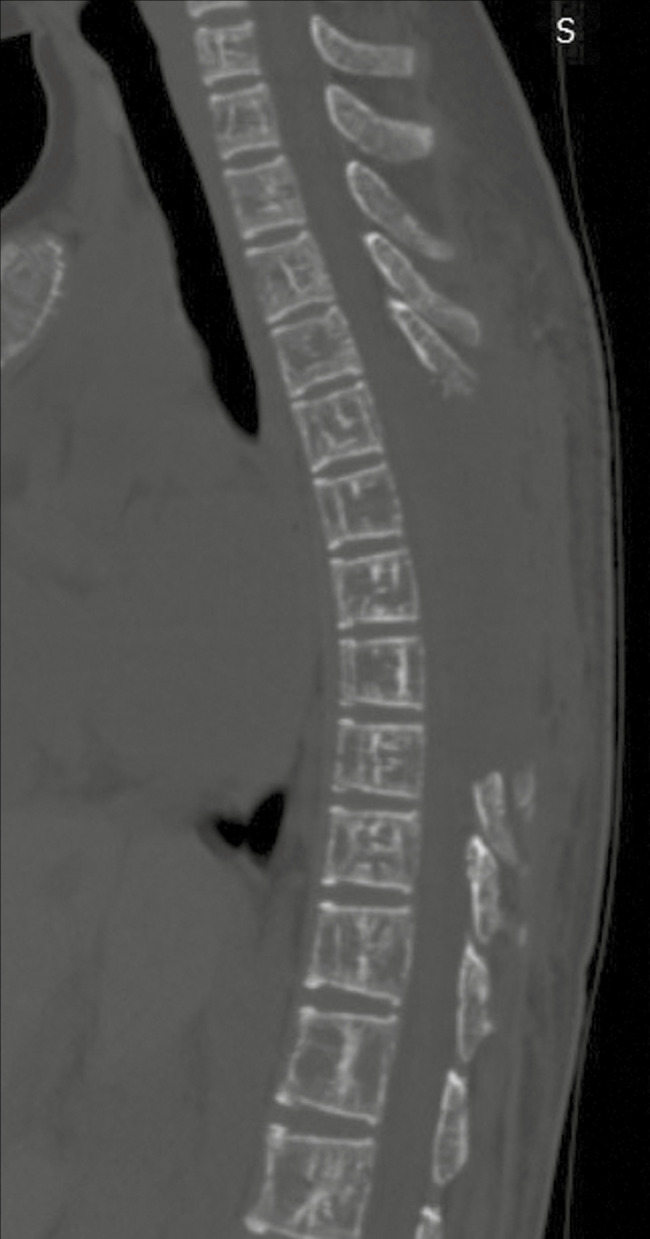

Case description: This report describes a young male with thalassemia major, who presented with symptomatic cord compression due to a thoracic intraspinal lesion. It was surgically excised and diagnosed as a case of EMH. The boy recovered fully and has been asymptomatic for six months now.

Conclusion: The occurrence of EMH in the thoracic spine is uncommon, whereas symptomatic cord compression as a result of it is even more unusual. Magnetic resonance imaging (MRI) is the diagnostic imaging of choice and treatment options that can be offered are surgical decompression, radiotherapy, hydroxyurea, and transfusion of packed red blood cells (RBCs).